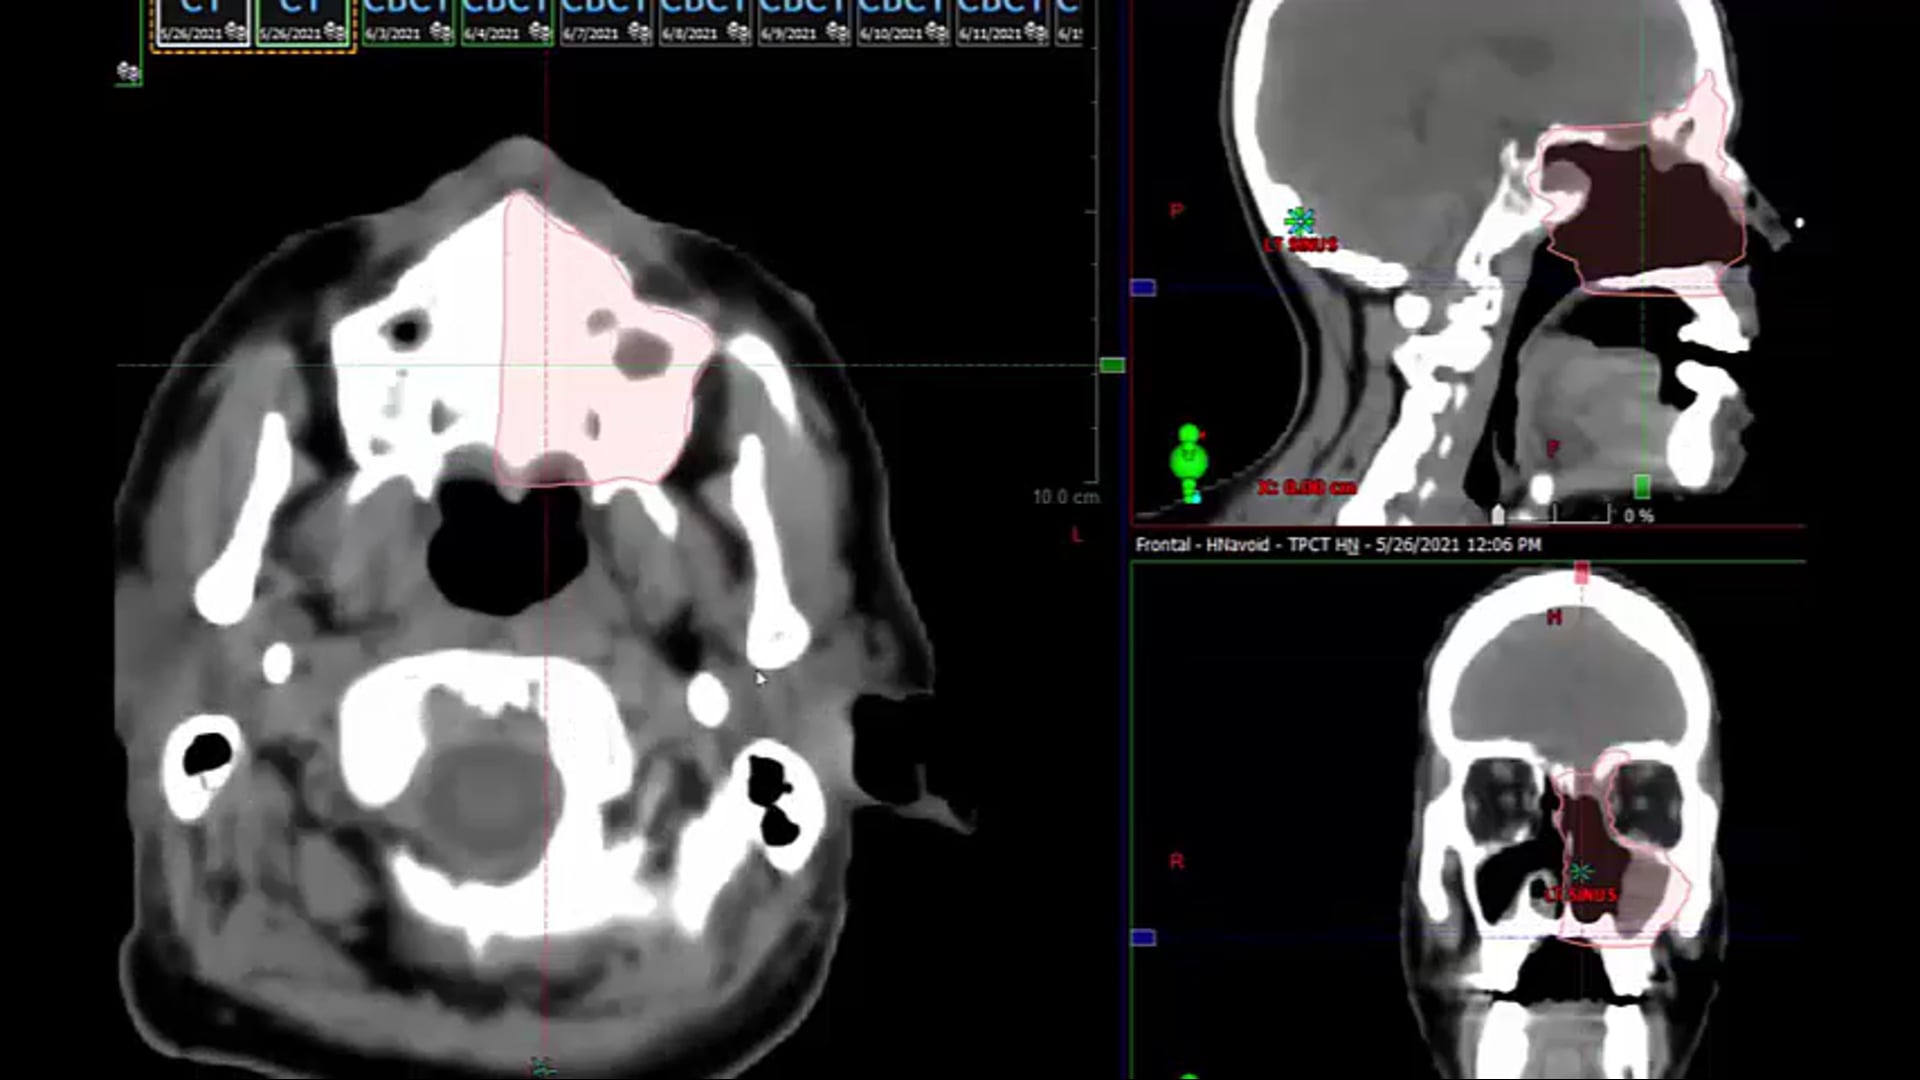

02/16/2023 - Dr. Cessal Kainickal - Radiation Oncology - India Head & Neck

PPF, maxilla, posterior, anterior, lateral, inferior, superior, medial, pterygopalatine ganglion, pterygomaxillary fissure, infratemporal fossa, ITF, PNI, sphenopalatine foramen, foramen rotundum, cavernous sinus. vidian canal, pterygoid canal, vidian nerve, artery, vein, pharyngeal canal, inferi...